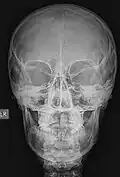

..jpg)

La imagen anterior es una imagen del cerebro. Es una prueba que permite el diagnóstico del trastorno de Parkinson. Se trata de una imagen tomográfica (SPECT).